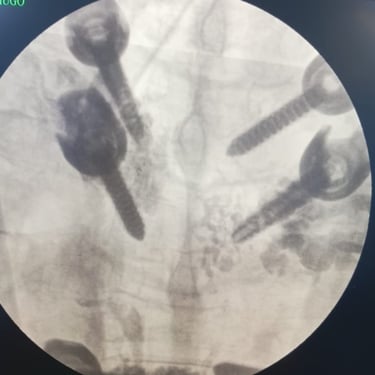

🧠 Fractura Vertebral Lumbar: Estabilización Segura con Fijación Transpedicular (FTP).

La fractura vertebral lumbar genera inestabilidad y dolor severo. La artrodesis con fijación transpedicular es una técnica quirúrgica eficaz que estabiliza la columna, previene desplazamientos vertebrales y mejora la recuperación funcional del paciente.